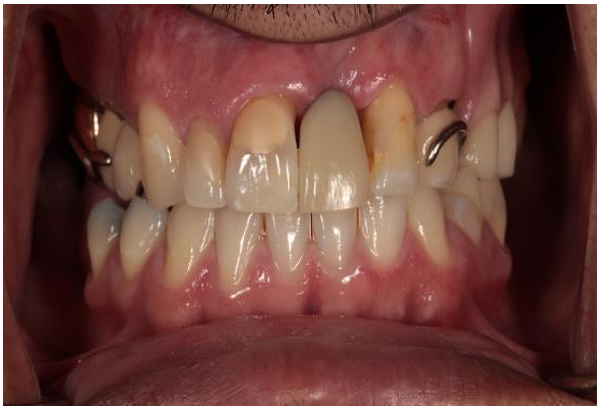

Case A 56-year-old male presented to a prosthodontic practice with an existing maxillary cast metal framework obturator. The current prosthesis restored the patient’s left maxillary posterior teeth and obturated the resected section of the patient’s palate which was lost due to oral cancer 15 years prior. The patient recently underwent removal of a single maxillary incisor (#9) due to loss of periodontal support and mobility. The existing obturator was well designed and provided the necessary retention, stability and support required for restoring the missing posterior segment, yet the missing tooth was not replaced (Fig. 1). The patient wanted to replace his missing maxillary central incisor; however, he did not want to replace his obturator which was only a year old.

Figure 1: Pre- treatment frontal MIP with obturator.